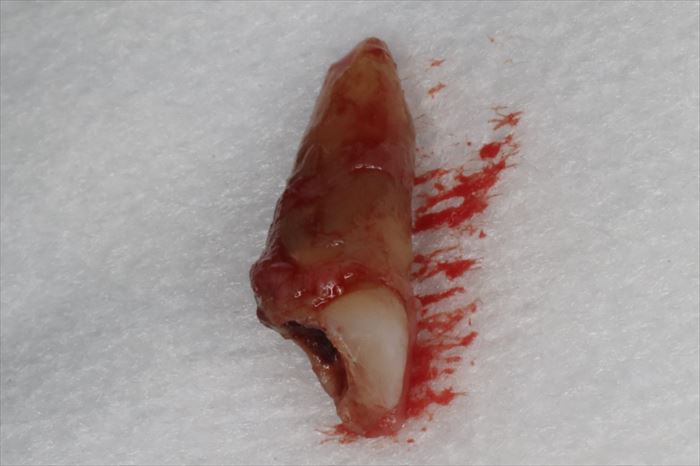

無事に抜歯を終えました。

神経(歯髄)を取って年月が経っている歯は、血液による栄養供給が絶たれるため変色し脆弱になっていきます。

歯の歯髄をいかに生かしたままにしておくかが大変重要です。安易に歯髄を取ってはいけません(根管治療)。

そういった意味では根管治療は万能ではなく、時限的な延命処置と私は考えます。